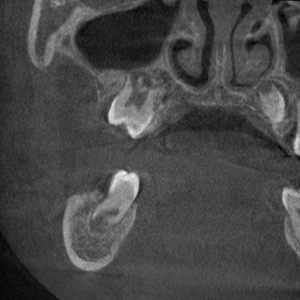

使用装置:モリタ社製ベラビューX800

2021年7月に歯科口腔外科系の撮影を行うパントモCT装置が新たに導入されました。

この装置では、2次元的に歯や顎の撮影を行うオルソパントモ撮影や顎関節撮影に加え、3次元で立体的に歯や病変を描出できるコーンビームCT撮影の機能も搭載されました。そのため従来の装置と比較して、より画質の良い、診断に有用な優れた画像検査が可能となります。

| 任意断面画像(横断像) | 任意断面画像(冠状断) | 任意断面画像(矢状断) |